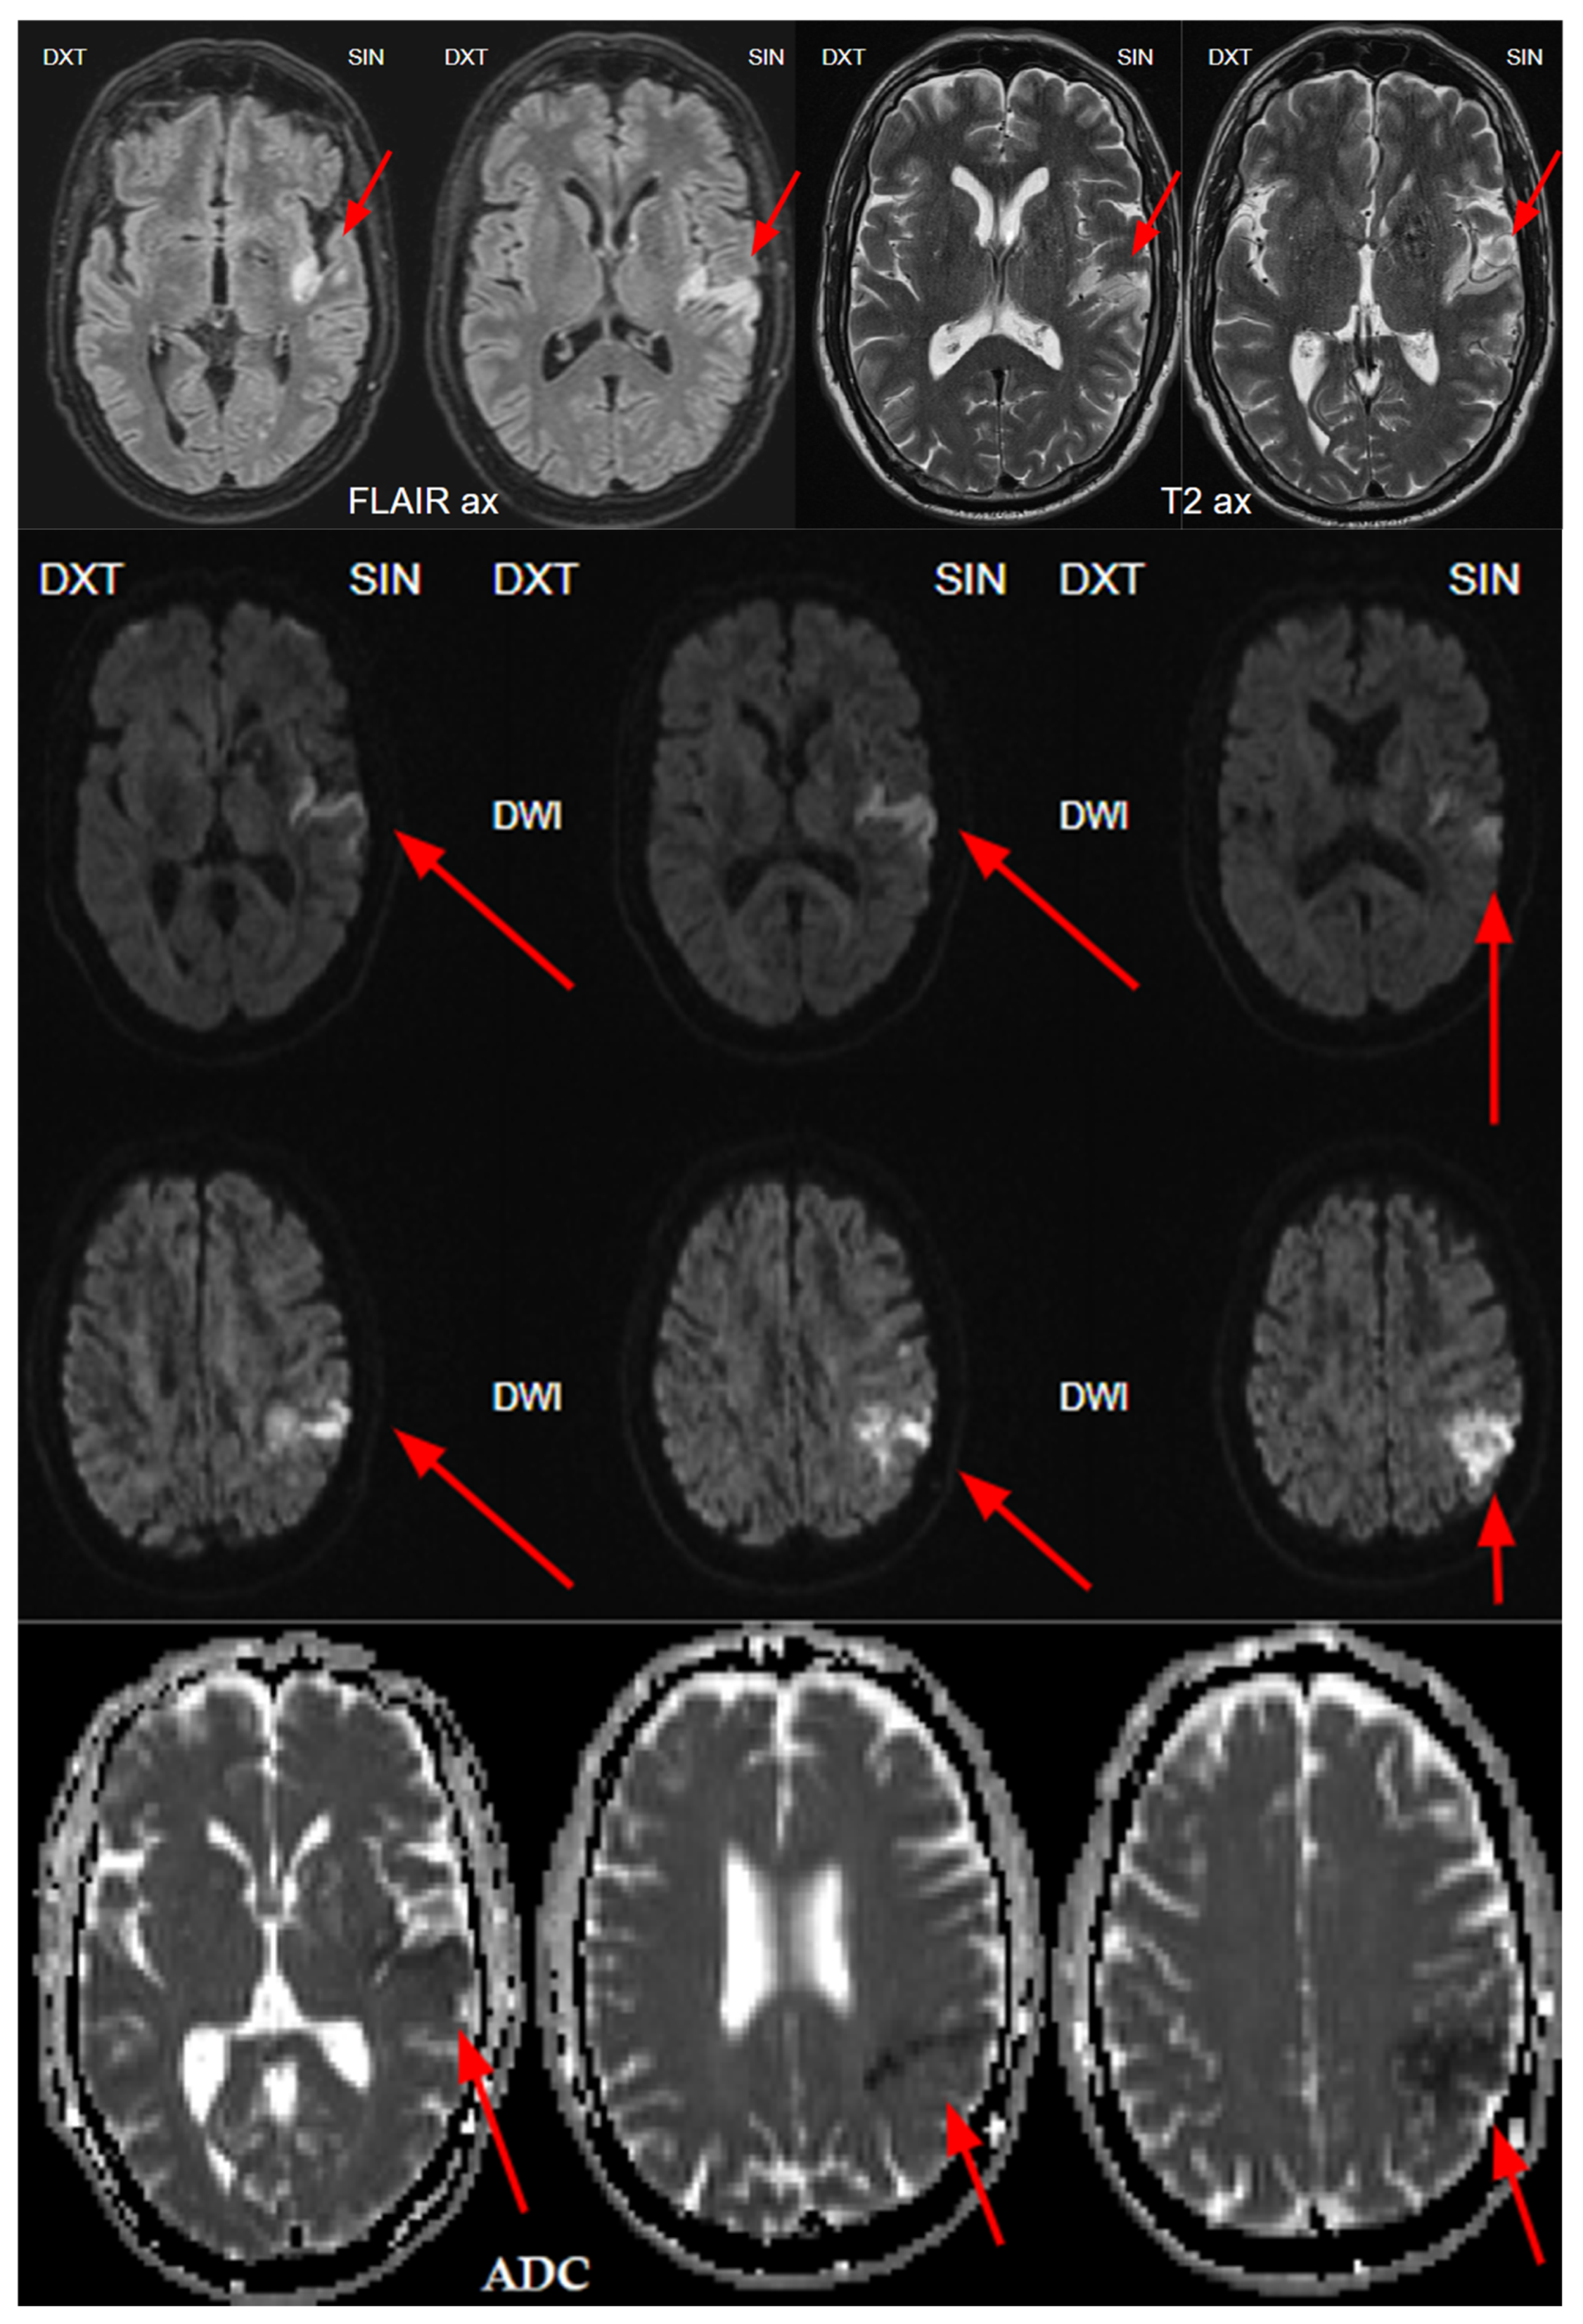

2. Case Presentation